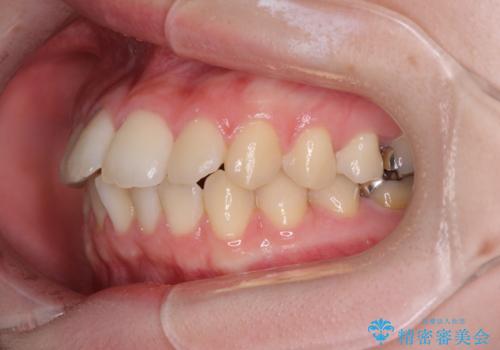

デコボコ歯列をきれいに インビザラインによる矯正治療

- 上下歯列全体のデコボコを気にして来院された患者様です。

主に下顎歯列全体の後方移動とIPR(歯と歯の間を削る)によってデコボコが解消するように設計し、インビザラインにより治療を行うこととしました。

1年半程度で終了するのではないかと予想しましたが、途中1年以上の来院がなく、トータルで3年の時間がかかってしまいました。

前歯のデコボコはより改善することが望ましい状態でしたが、患者様の希望により終了することとなりました。